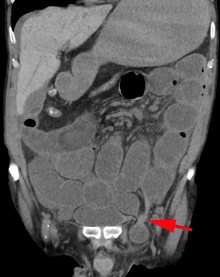

After the diagnosis is suspected, it is often confirmed by imaging. When assessed by ultrasound or cross sectional imaging with CT or MRI, the major differential in diagnosing indirect inguinal hernias is differentiation from spermatic cord lipomas, as both can contain only fat and extend along the inguinal canal into the scrotum.[9]

On axial CT, lipomas originate posterolateral to the cord, and are located inside the cremaster muscle, while inguinal hernias lie anteromedial to the cord and are not intramuscular. Large lipomas may appear nearly indistinguishable as the fat engulfs anatomic boundaries, but they do not change position with coughing or straining.[9]